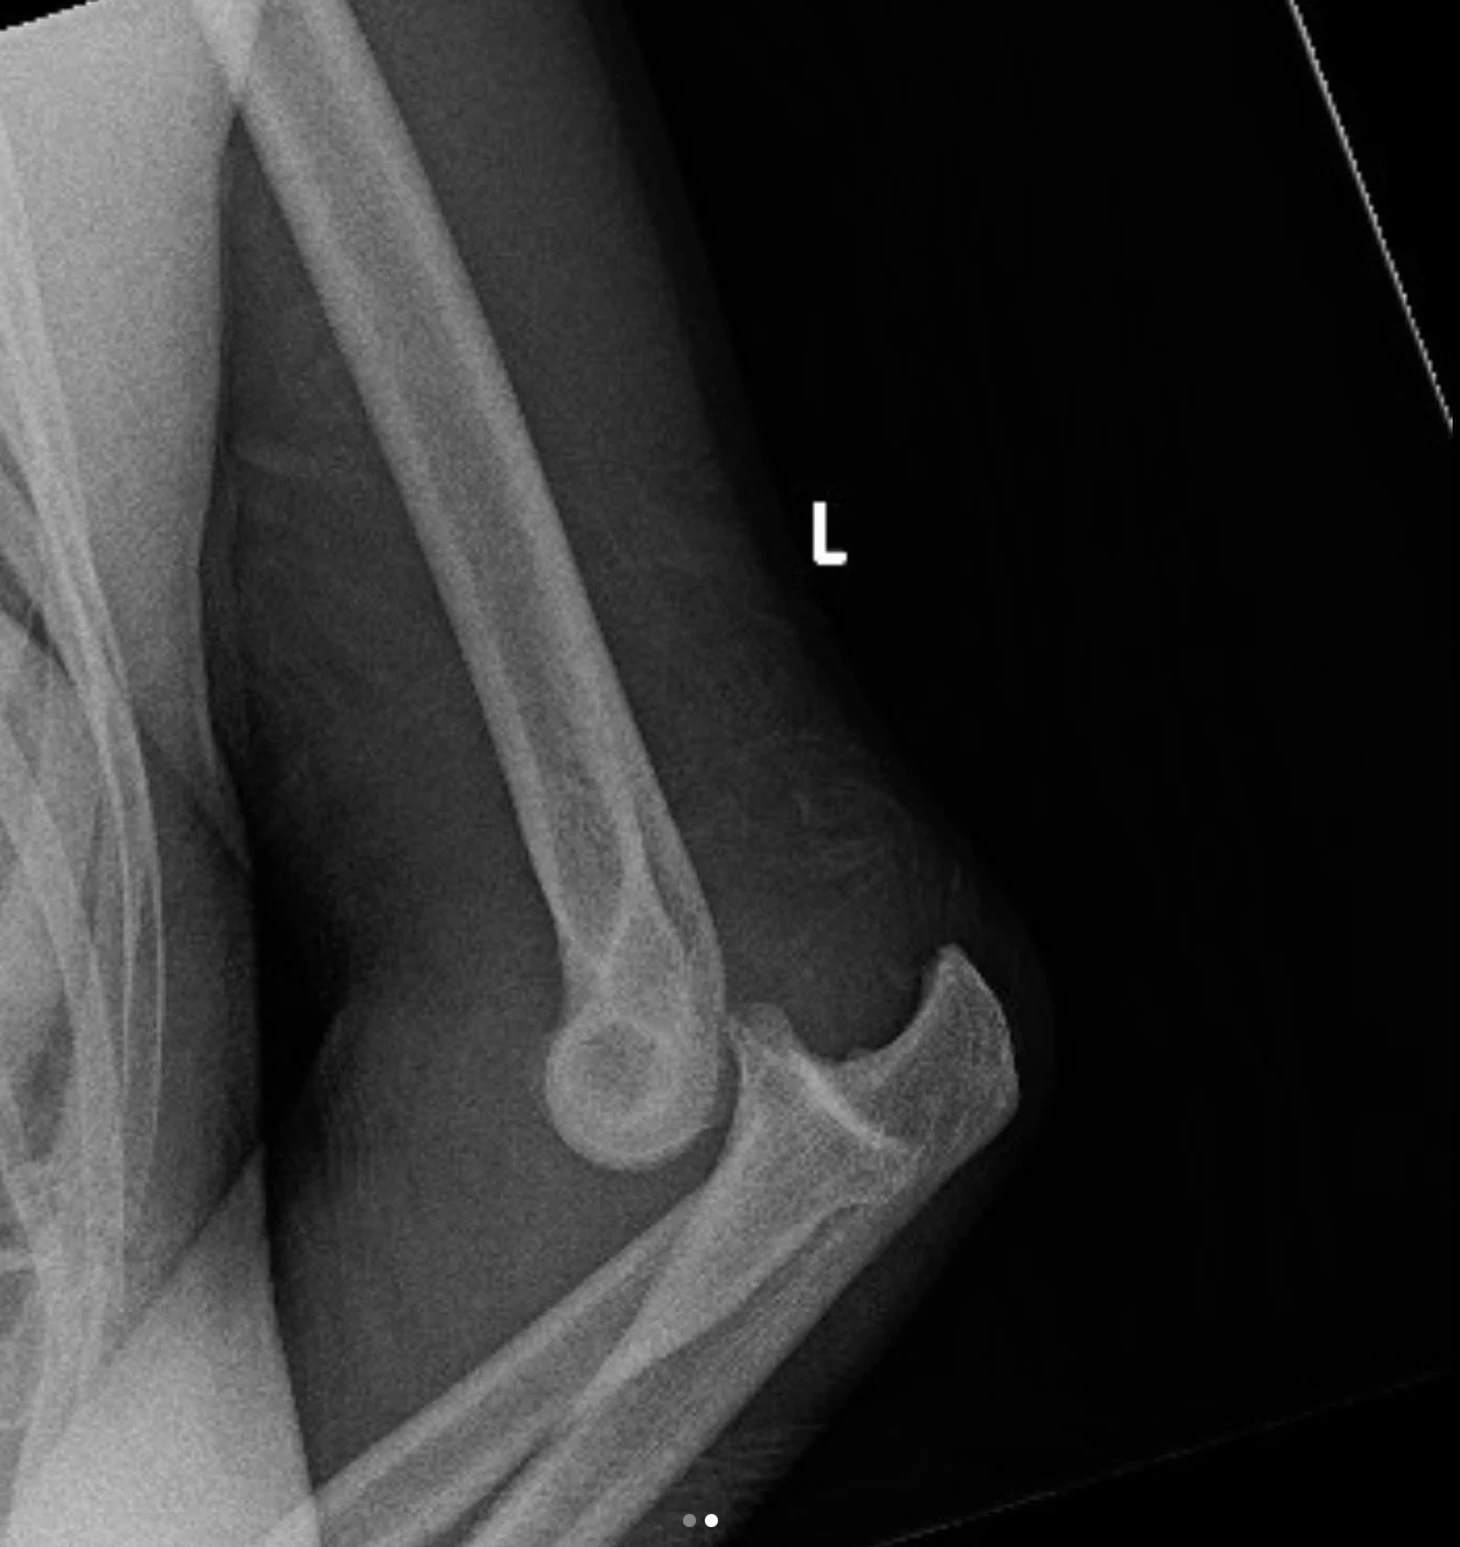

Дана Уайт выложил в соцсетях рентгеновский снимок руки Истелы Нунес – перелом.

Бразильянка получила перелом руки в поединке с россиянкой Викторией Дудаковой.